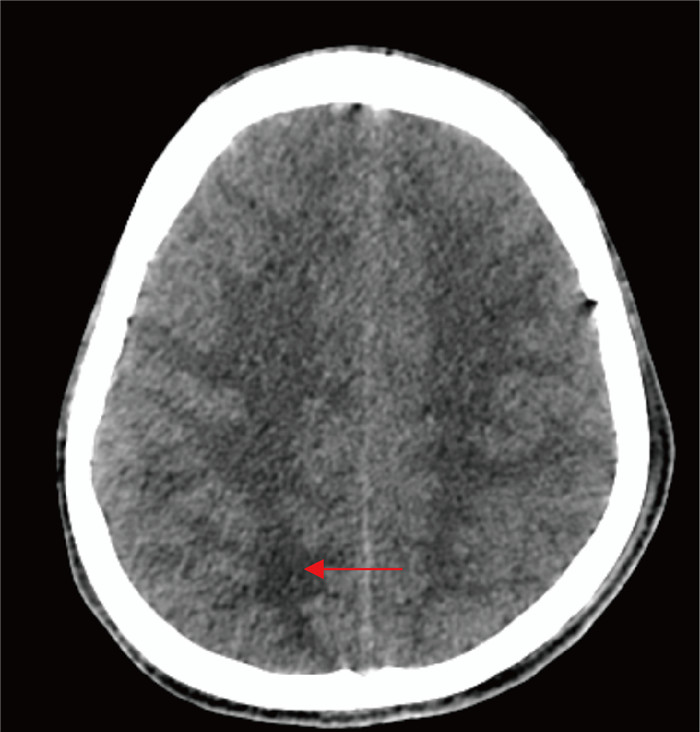

诊疗过程如下。3月24日,患者到院后查血常规示白细胞计数20.62×109/L↑,中性粒细胞百分比93.1%↑;C反应蛋白23.86 mg/L↑;降钙素原0.488 ng/mL↑;脑脊液测压大于320 mmH2O。脑脊液常规示白细胞335.2×106/L↑,潘氏试验2+;脑脊液生化示氯108.0 mmoL/L↓,葡萄糖 < 1.11 mmoL/L↓,脑脊液蛋白4 056.97 mg/L↑。头胸计算机断层扫描(computed tomography, CT)提示:1.考虑双肺弥漫性细支气管炎;左肺上叶尖后段、右肺下叶背段薄壁空洞,真菌性感染待排,请结合临床;2.脑室系统扩张,右侧顶叶皮层下片状低密度灶;3.左肺上叶散在钙化灶(见图 1~2)。3月25日晨经验用药予哌拉西林/他唑巴坦4.5 g q8h和莫西沙星0.4 g qd,16: 56脑脊液涂片结果显示:抗酸+ +(抗酸染色结果如图 3)。根据抗酸染色结果,临床医师立即予异烟肼片600 mg qd,利福平0.6 g qd,吡嗪酰胺片0.5 g qd,盐酸乙酰丁醇片0.75 g qd四联抗结核治疗。经过治疗,患者生命体征相对稳定,意识状态仍较淡漠,3月29日转至专科医院继续抗结核治疗。

| 图 2 患者脑部CT征象 Fig. 2 Brain CT signs of the patient |

| 图 1 患者胸部CT征象 Fig. 1 Chest CT signs of the patient |